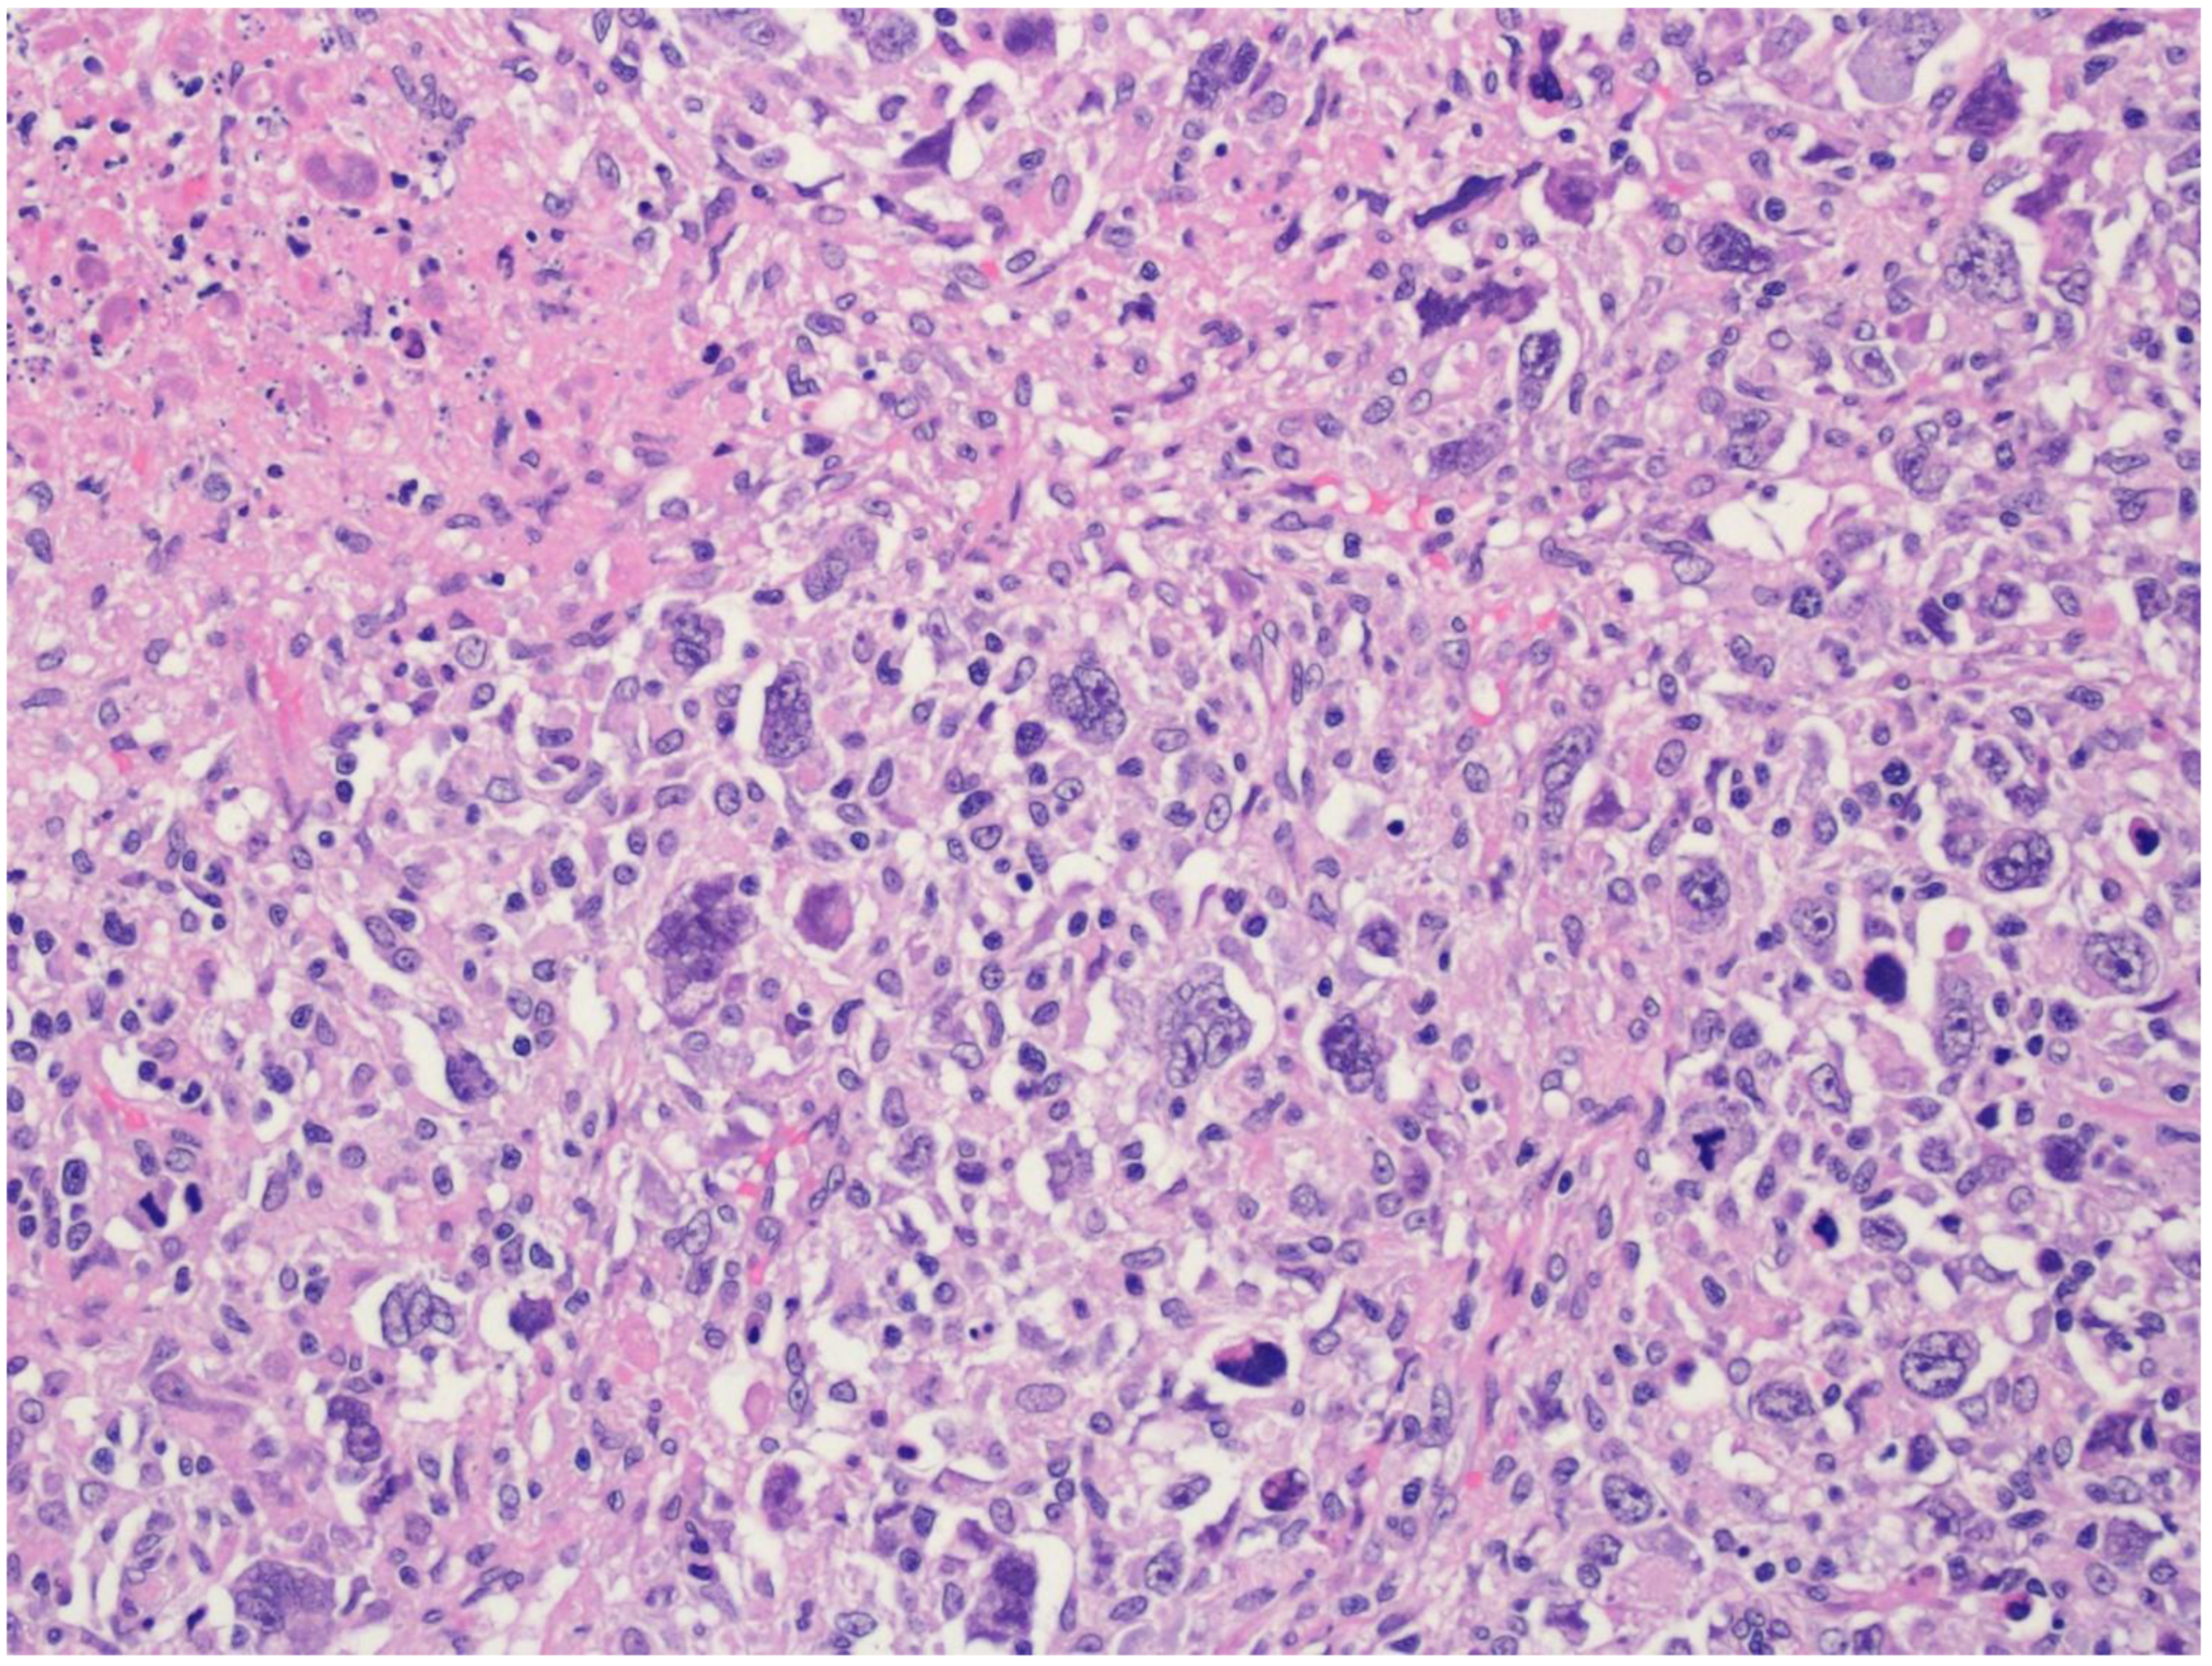

17. Intravascular Large B-Cell Lymphoma

| Intravascular large B-cell lymphoma |